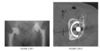

A sagittal fast spin-echo, T2-weighted fat-suppressed

MR image through the lateral joint compartment

(Fig. 2.14.3) shows high-signal-intensity areas in the

subchondral regions of the midportion of the lateral femoral condyle and the posterolateral tibial plateau,

the so-called “kissing contusions”

MRI features of the torn ACL include an irregular

or wavy contour with decreased angulation on the

sagittal images (i.e., “lying down” or vertically ori-

ented ACL), increased signal intensity on all MRI

sequences in the region of the ACL (i.e., so-called

“pseudo-mass”), posterior displacement of the lateral

meniscus (i.e., “uncovered lateral meniscus” sign),

loss of the normal obtuse curvature with increased

angulation of the posterior cruciate ligament, undu-

lation of the patellar tendon, and the “empty notch”

sign, which is also seen on arthroscopy.

Bone

impaction from transient subluxation results in

the characteristic osseous contusions involving the posterolateral tibial plateau and midportion of the

lateral femoral condyle (i.e., “kissing contusions”).